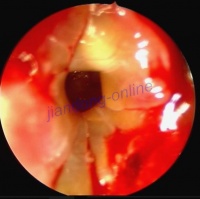

鼻息肉nasal polyp,耳鼻喉科疾病,发生于鼻腔内的赘生物。中医称鼻痔。鼻息肉多因平素嗜食辛辣炙煿厚味,蕴生湿热;上蒸于肺,结滞鼻窍;或风热邪毒侵袭肺经肺气不得宣畅,积聚鼻窍所引起。主要表现为鼻窍内有一个或多个赘生物,表面光滑,色淡白或淡红,触之柔软而不痛 ,伴有持续性鼻塞嗅觉减退,鼻涕增多,头痛 ,头昏等 。治疗以外治为主,可用硇砂散、明矾散等,以水或香油调匀,敷于息肉根部。内治宜清热泻湿,宣肺散结,方用辛荑清肺饮等。

鼻镜检查可见一个或多个表面光滑、灰色或淡红色的如荔枝肉状、半透明肿物,触之感觉柔软、不痛,可移动,一般不易出血。早期息肉因其体形小,故有时须用l%麻黄素生理盐水下鼻甲收缩后方能发现。后鼻

镜检查和鼻内窥镜检查对明确鼻息肉的部位和范围有重要意义。x线鼻窦拍片也属必要。